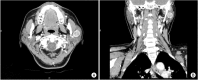

Basal cell adenoma (BCA) is a rare, benign neoplasm that most frequently arises in the parotid gland. We treated a 54-year-old female patient with BCA that had developed in the deep portion of the left parotid gland. The patient presented with gradual facial swelling with no other symptoms. We performed a total parotidectomy to excise the mass, but we preserved the facial nerve. Histopathology revealed a well-encapsulated mass. The tumor was composed of islands of comparatively uniform, small, dark, basaloid epithelial cells in the stroma. Histologic and immunohistochemical studies concluded that the BCA tumors were mostly trabecular. Postoperatively, there was no facial nerve weakness, and the tumor did not recur during the 24-month follow-up period.